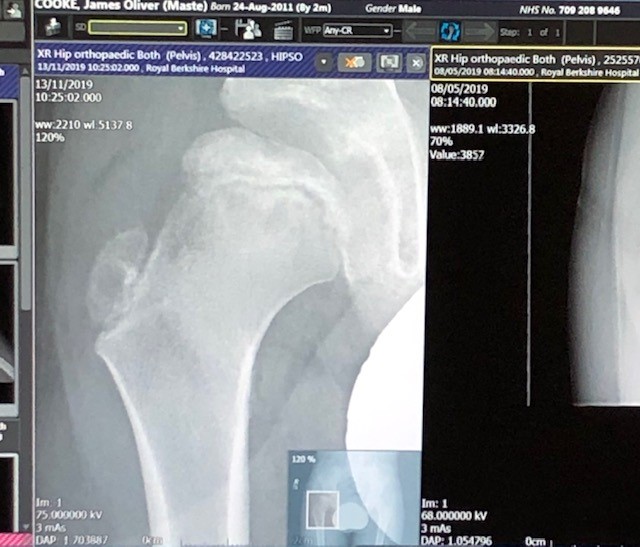

“Progress” of Perthes throughout 2019